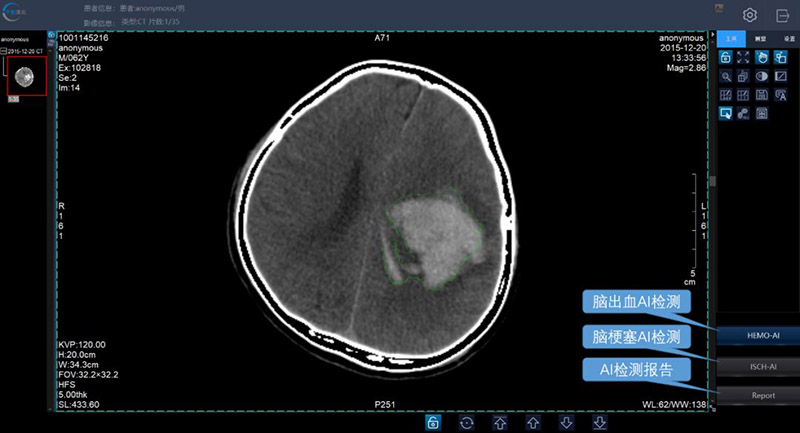

千图深云AI平台发布,集成脑出血、脑梗塞模块,检测结果达专业医生水平

Trilimage AI从CT设备自动接收影像数据,通过阅片界面一键进行脑梗塞或脑出血的AI分析。分析完成后,病灶区域会被精确标注,并一键生成AI报告。

脑出血的AI检测(标注区域为病灶区域)

为提供给医生详细的病灶信息,研发团队利用公司自有的中国人群大脑模板进行脑区配准,医生可从报告中获得详细的病灶体积、病灶位置、每个脑区中的病灶体积等关键信息,这些信息正是临床医生所迫切需要的。

目前,脑医生在脑卒中的CT影像诊断准确率已超過80%,更重要的是,作为国内首个基于CT影像数据的脑卒中智能诊断系统,脑医生更符合医生的使用习惯,临床应用更为广泛。